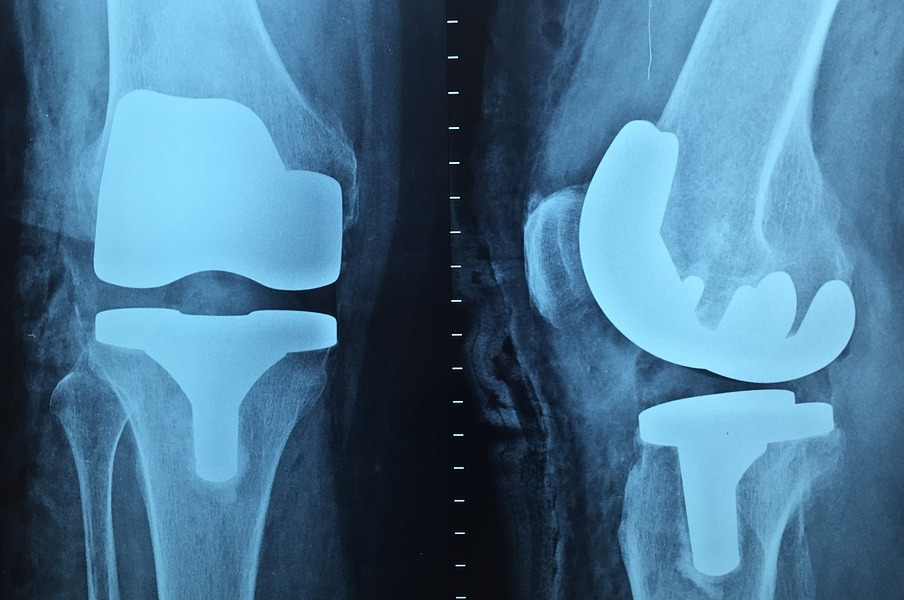

2. 골다공증 예방

뼈의 강도가 약해져 골절이 일어나기 쉬운 골다공증은 노인 뿐만 아니라 중장년층에게서도 발생하고 갈수록 발병률도 높아지고 있습니다. 식초는 뼈에 이로운 칼슘과 철분을 이원화해 몸에 잘 흡수되도록 도우므로 뼈를 튼튼하게 만드는데 기여합니다.